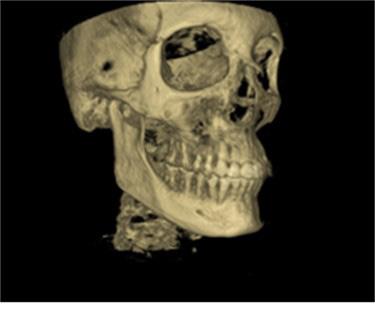

Lateral Cephalometric radiogram and tracing revealed robust lower airway (18.0/15mm), CVMS 6, maxilla and mandible are prognathic (SNA - 93° and SNB - 84°), Class II skeletal (ANB –9.0 mm, Witts – 9.0 mm). The patient was hyperdivergent (NS/ GoM – 30°, ALFH - 83 mm!!), protrusive maxillary incisors (U1/ SN – 117.0°), mandibular incisors were within the norm (L1/GoM 95.0°) and Harvold Δ was 30 mm. The soft tissue profile (lips) was convex (Figure 5-C, D).

There is a new digital 3D imaging known as cone-beam volumetric tomographs (CBVT) which can provide 3D views of the cranium, jaw and teeth. As more of this type of x-ray equipment is developed and released on the market, they will provide improved quality images with lower exposure to x-rays as well as at a lower cost for the patients. CBVT, due to their 3D imaging capability, are particularly helpful for studying the jaw joints, the nasal cavities, sinuses and the airway at the back of the throat.